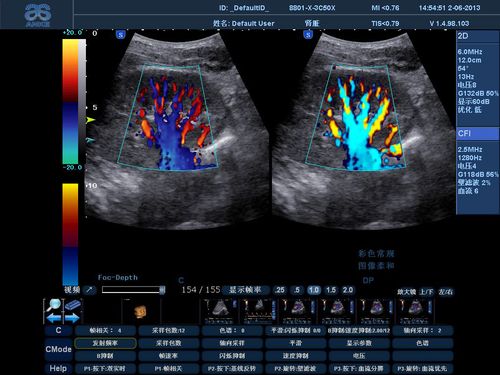

彩色多普勒超声心动图

多普勒超声心动图

二维彩超